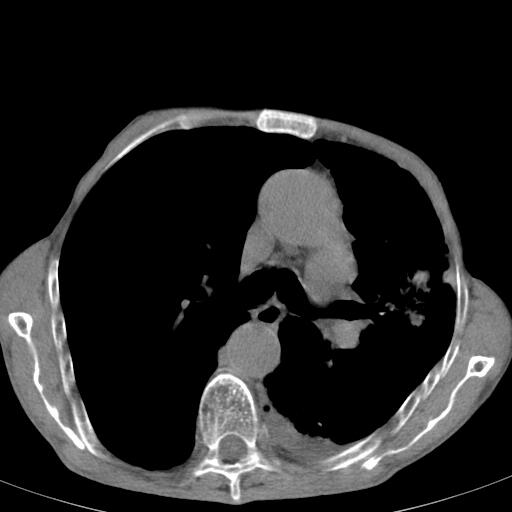

患者78岁,咳嗽胸闷一年余,近月来左侧胸痛;

建议强化,首先考虑左肺癌胸膜转移。

左侧少量胸腔积液,局限胸膜增厚,结合病史,考虑慢性肺炎.

患者左侧胸廓塌陷说明是长期病变,考虑tb性胸膜炎可能性大,另外有明显的肺气肿,建议行结核菌素实验,或者增强扫描

1.慢支肺气肿。2.左肺感染,建议治疗后复查。3.左侧少量胸水。

1.慢支肺气肿。2.左肺感染,建议治疗后复查,待除外继发性肺结核合并感染。3.左侧少量胸水。

1)考虑左肺慢性感染性病变(结核可能)。2)左肺上叶周围型肺癌不排除;建议追踪复查。3)肺气肿。4)左侧胸腔积液,左侧胸膜增厚、粘连。